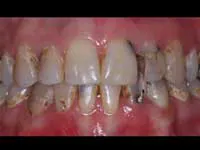

Less than one-half of the coronal tooth structure remaining (Figs. 1-6)

It is my opinion, regardless of the other factors present, that it is still advisable to place a post or posts in such teeth. Endodontically treated teeth with less than one-half of the coronal tooth structure remaining have a reduced chance of long-term service, and patients should be so advised as the treatment plan is developed.

Quality of remaining tooth structure

Assuming that there is a significant amount of coronal tooth structure remaining, the quality of the remaining tooth structure should be considered. Often, remaining tooth structure has discolored areas, slightly demineralized areas, cracks, undermined areas, or other negative characteristics. Removal of tooth structure with these characteristics allows a realistic and necessary appraisal of the amount of viable tooth structure remaining. After removing the affected areas, the same suggestions stated in the previous section on quantity of tooth structure remaining apply. Posts are often indicated.